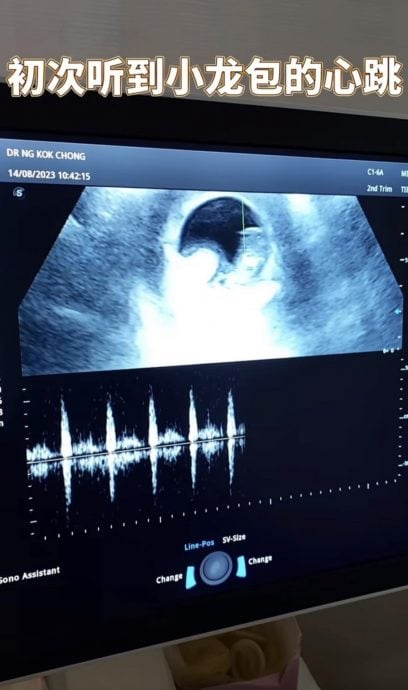

(吉隆坡17日讯)爱FM DJ叶恩慈曾表示自己是“不婚主义者”,日前晒出婚照在文末标注“只有生小孩才会让我结婚”,认了自己是先上车后补票。不过,她自曝半年前开始决定生小孩,开始备孕,并为肚子里的宝宝取名为“小龙包”。

叶恩慈晒出与圈外老公的婚照,直接双喜临门开心宣布结婚并怀孕,文末更标签:“我的爱情不需要婚姻”、“但小孩法律地位需要”、“这是我给小龙包(宝宝小名)的礼物”。